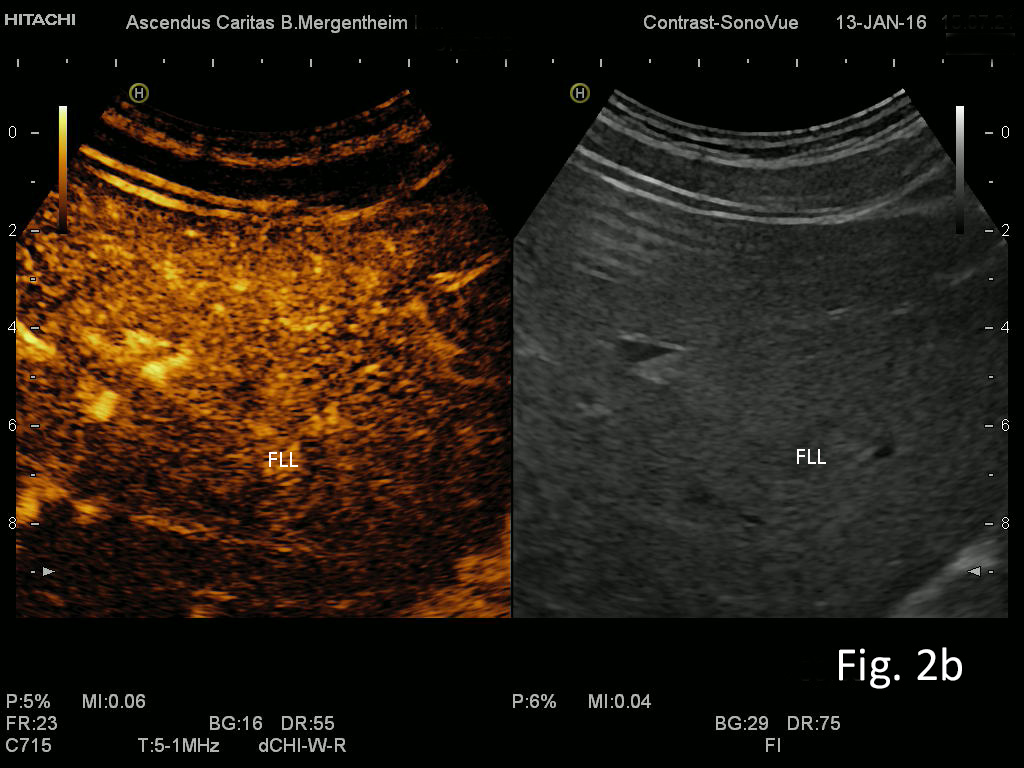

Figure 2: Focal liver lesion using B-mode (a) and contrast enhanced ultrasound (CEUS) in the arterial (b), late phase (c) and CEUS using time intensity curve analysis (TICA) (d). The B-mode ultrasound showed an isoechoic lesion with transducer distal shadowing, somewhat unspectacular. CEUS showed early and slightly hyperenhancing features in the arterial phase and pronounced wash out in the portal venous and late phases indicating metastases and excluding hemangioma [(1)]. The TICA image on the right side of the screen differentiates the initially hyperenhancing lesion (red line) in comparison to the surrounding liver parenchyma (yellow line). In the portal venous phase the red line crosses downward in comparison to the liver parenchyma (yellow line), indicating metastasis [(2-5)].